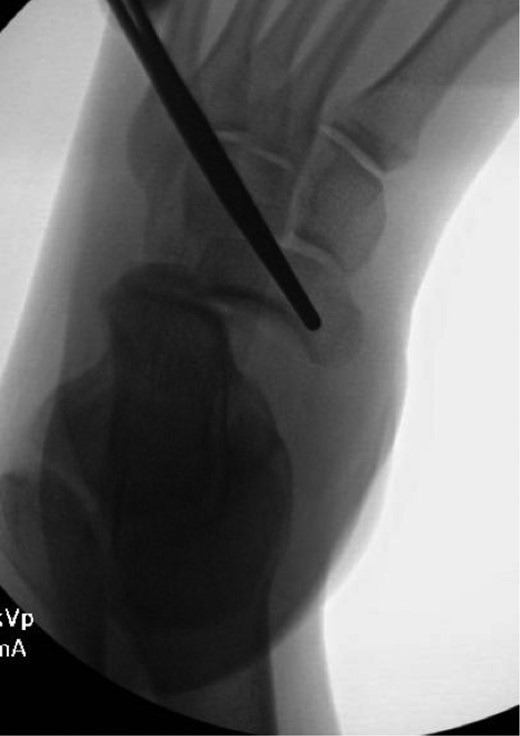

Once general anesthesia was induced, closed reduction was attempted using axial traction with the knee in flexion. Closed reduction was unsuccessful once again (Fig. 3) so the decision was made to attempt open reduction. An anteromedial approach was used dissect down to the talonavicular joint. Retractors were placed with care to avoid injury to tibialis anterior tendon or superficial peroneal nerve. The joint capsule was seen to be disrupted and further exposure revealed a thin, coronal fracture of the anteromedial aspect of the talar head measuring roughly 2 cm in length and 6 mm in thickness (Fig. 4). Once this fragment was removed, the subtalar and talonavicular joints were easily reduced. It was thought that this incarcerated fragment was the likely cause for the unsuccessful closed reduction. The talar head fragment was unamendable for stabilization due to its small size with poor healing potential, thus it was removed. The talonavicular joint was then percutaneously pinned in retrograde fashion with three K-wires (Fig. 5) to maintain anatomic reduction of the subtalar and talonavicular joints and the foot was splinted. At 2 weeks follow-up the patient was doing well and radiographs revealed no interval loss of reduction (Fig. 6).

Some studies suggest obtaining a CT scan of the ankle postreduction to check anatomic reduction as well as assess for other fractures [8, 9]. In our case, we did not obtain a postreduction CT scan. The subtalar and talonavicular joint were well visualized intraoperatively and were found to have no other associated fractures. In addition, anatomic reduction was obtained and under direct visualization and confirmed with fluoroscopy. Due to residual instability following reduction, K-wires were used to stabilize and hold the reduction. K-wire transfixation is supported in the literature for subtalar dislocations which tend to redislocate [10]. In other cases, where the joint is stable after reduction, there is no need for fixation.